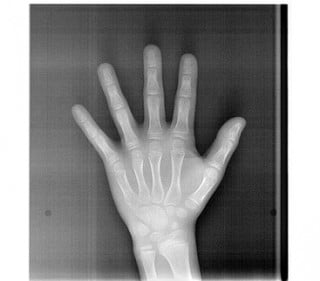

パノラマ(お口全体のレントゲン)・セファロ(お顔・手のレントゲン)・口腔内写真(現在の歯並びの写真)・顔写真・歯の型取り

をして丁寧に状態の確認を行います。

セファロ

上下のあごの大きさ/上下のあごのズレ/あごの形/歯の傾斜角/口元のバランス など

顔貌の対称性/歯列幅/関節の形/咬合平面の傾斜 など

成長発育の段階を確認

手の骨(足の骨)は成長に合わせて形、大きさを変えていくことが分かっています。成長の段階を知ることで、治療開始時期の決定や使用装置の効果を予測。